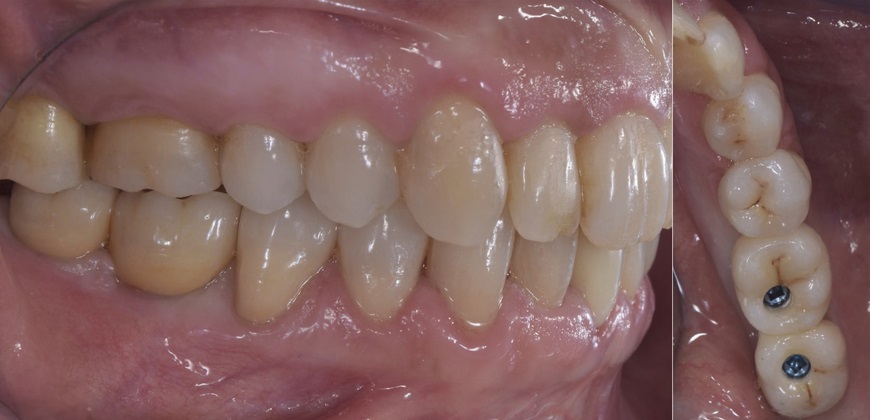

- Pacjentka R.C., lat 50, zgłosiła się do naszego gabinetu z prośbą o możliwość ponownego przykręcenia dwóch koron na implantach wprowadzonych w pozycjach 46 i 47, które według niej się odkręciły.

Coraz częstszą sytuacją jest potrzeba rehabilitacji protetycznej na implantach, których specyfiki nie znamy. Włoski producent rozwiązań retencyjnych Rhein’83 (Bolonia, Włochy) od wielu lat produkuje elementy, które są dostosowane swoimi połączeniami do implantów, na które są przykręcane, aby zagwarantować patryce retencyjne dla protez ruchomych u pacjentów, którzy nie mogą przedstawić dokumentacji pozwalającej zidentyfikować model i średnicę wprowadzonych w podłoże protetyczne implantów zębowych.

Tą samą metodą można dzisiaj realizować prace protetyczne przy użyciu łączników OT Equator (do rozwiązań ruchomych lub stałych), w ramach [...]